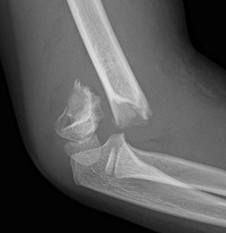

Una fractura supracondílea es una lesión común en el mundo de la traumatología pediátrica. Se trata de una ruptura que ocurre en el hueso del húmero, justo por encima de